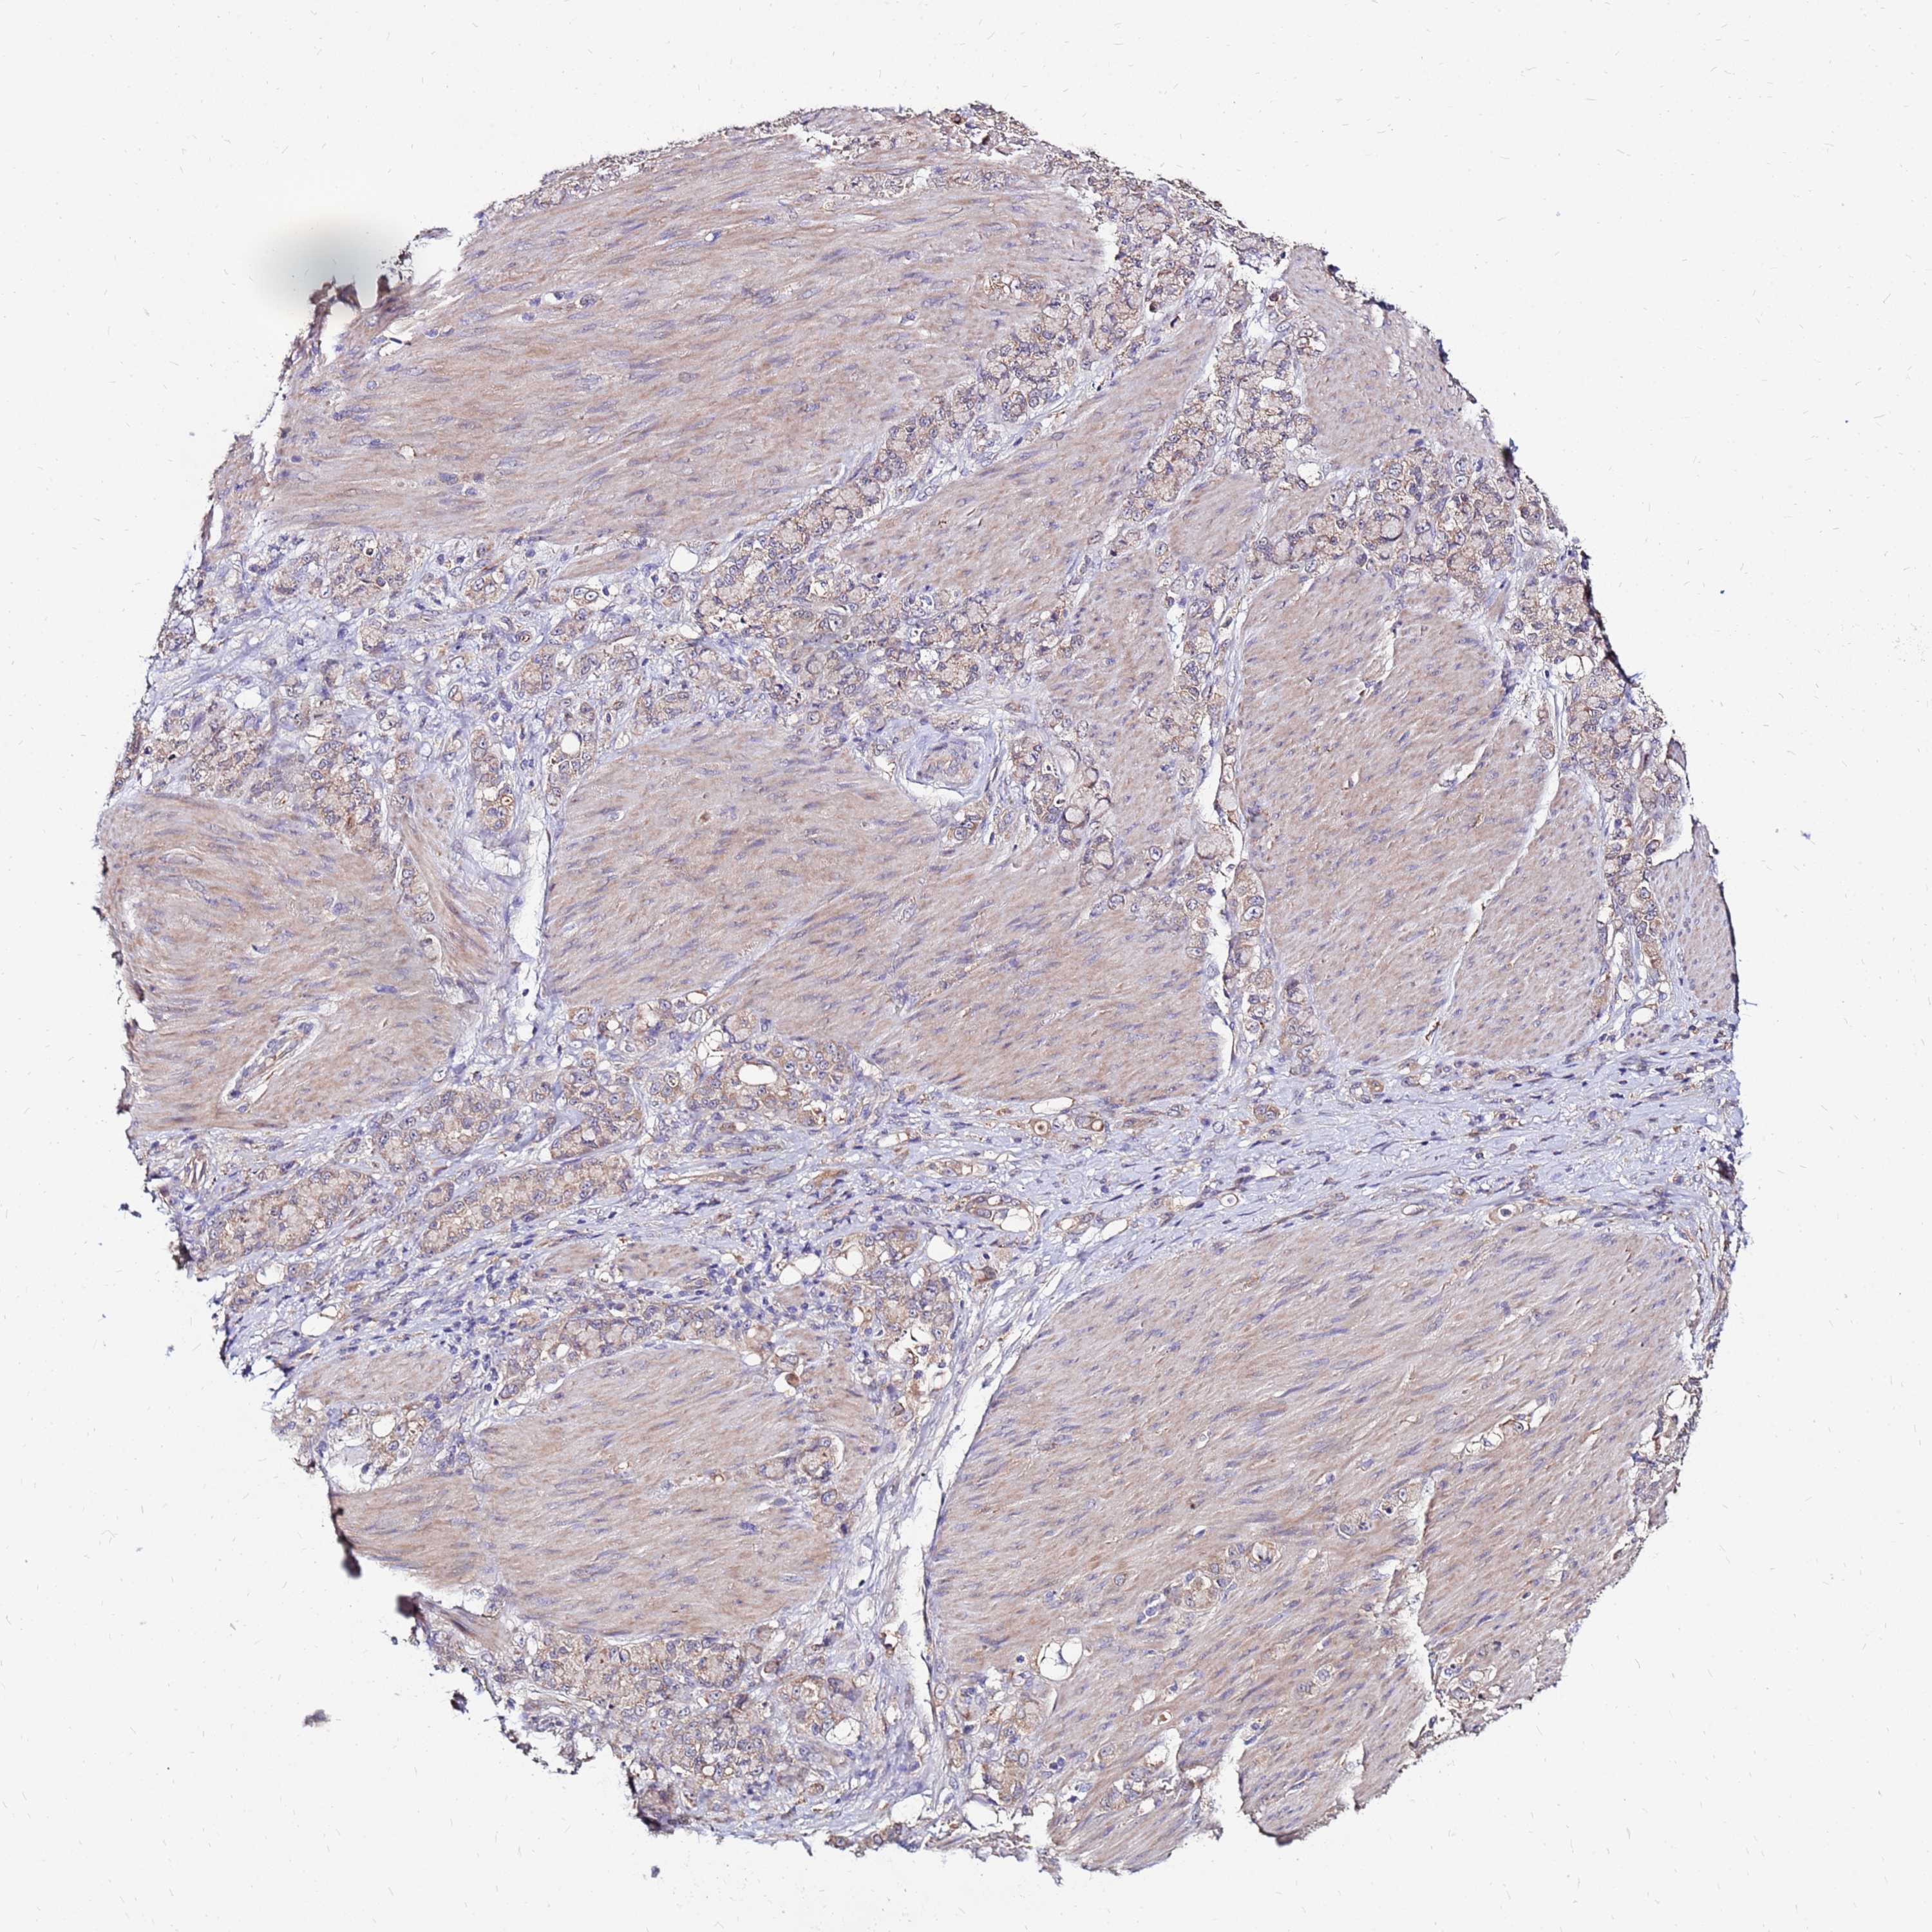

STOMACH CANCER - Protein expressioni

A mouse-over function shows sample information and annotation data. Click on an image to view it in a full screen mode. Samples can be filtered based on level of antibody staining by selecting one or several of the following categories: high, medium, low and not detected. The assay and annotation is described here.

Note that samples used for immunohistochemistry by the Human Protein Atlas do not correspond to samples in the TCGA dataset.

Antibody stainingi

Antibody staining in the annotated cell types in the current human tissue is reported as not detected, low, medium, or high, based on conventional immunohistochemistry profiling in selected tissues. This score is based on the combination of the staining intensity and fraction of stained cells.

Each image is clickable and will lead to virtual microscopy that enables deeper exploration of all samples and also displays staining intensity scores, fraction scores and subcellular localization as well as patient and tissue information for each sample.

Antibody HPA044188

Antibody HPA045619

Antibody HPA045699

Staining

High

Medium

Low

Not detected

Intensity

Strong

Moderate

Weak

Negative

Quantity

>75%

75%-25%

<25%

None

Location

Nuclear

Cytoplasmic/membranous

Cytoplasmic/membranous,nuclear

Adenocarcinoma, NOS